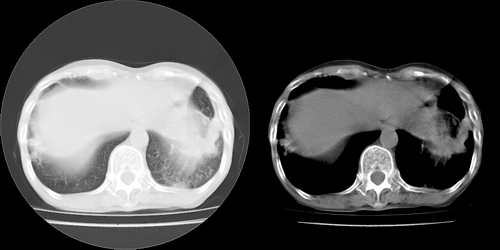

以下是引用lihuuuu在2006-7-18 18:16:00的发言:[br]支持肺结核诊断[br]本病例符合结核“三多”“三少”特征(多病灶、多形态、多钙化、少肿块、少堆积、少增强)中的前五个特征,另外左下叶背段有不张样改变-考虑伴有支气管内膜结核所致段不张。

以下是引用yang4132在2006-7-18 10:04:00的发言:[br]两肺多发 多形态病变,部分半纤维条索和斑点壮钙化,胸膜肥厚粘连,考虑结核。